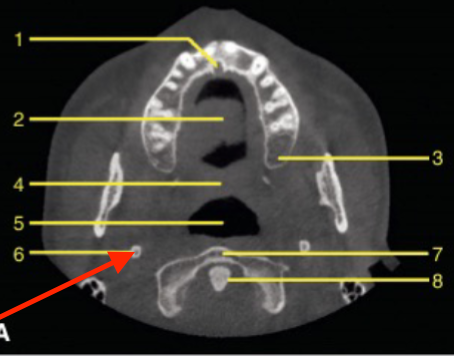

axial

what plane is this

level of maxilla (above maxillary teeth)

at what level is this

mandibular condyle

what structure is this

coronoid process